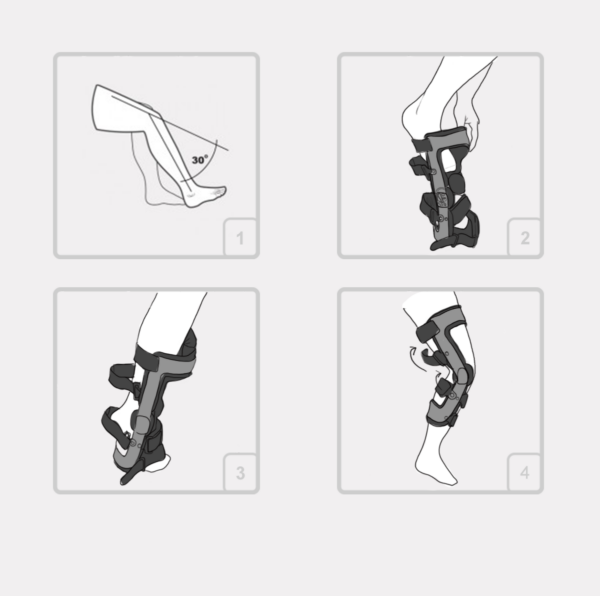

INSTRUKCJA ZAKŁADANIA ORTEZY „RAPTOR 2RA“

1. Odblokować zegary boczne w celu uzyskania maksymalnego zakresu zgięcia i wyprostu ortezy.

2. Porozpinać i powysuwać z klamerek poszczególne pasy mocujące.

3. W celu wyeliminowania przypadkowego plątania się pasów, po odpięciu i wysunięciu danego pasa z klamerki, należy powtórnie przypiąć do niego zakończenienie rzepowe.

4. Ustawić kończynę pacjenta w zgięciu ok. 120 stopni i wsunąć ortezę na kończynę dolną.

5. Przepleść przez klamrę poliamidową i zapiąć przedni dolny pas goleniowy oznaczony numerem (1)

6. Ustawić zegar ortezy dokładnie w osi stawu kolanowego , przepleść przez klamrę i dopiąć tylny pas udowy oznaczony numerem (2)

7. Przepleść przez klamrę i dopiąć tylny pas udowy oznaczony numerem (3) Uwaga; napięcie tylnego pasa powoduje przesunięcie zegara do tyłu, i dlatego należy tak dobrać napięcie pasa alby po jego zapięciu zegar znajdował się dokładnie w osi stawu kolanowego.

8. Zgiąć staw kolanowy do ok 70 stopni i w takiej pozycji mocno dopiąć przedni pas podkolanowy oznaczony numerem (4), zwracając uwagę by miękka osłona antypoślizgowa znajdowała się na środku goleni.

9. Wyprostować kończynę i dopiąć tylny pas łydkowy oznaczony numerem (5).